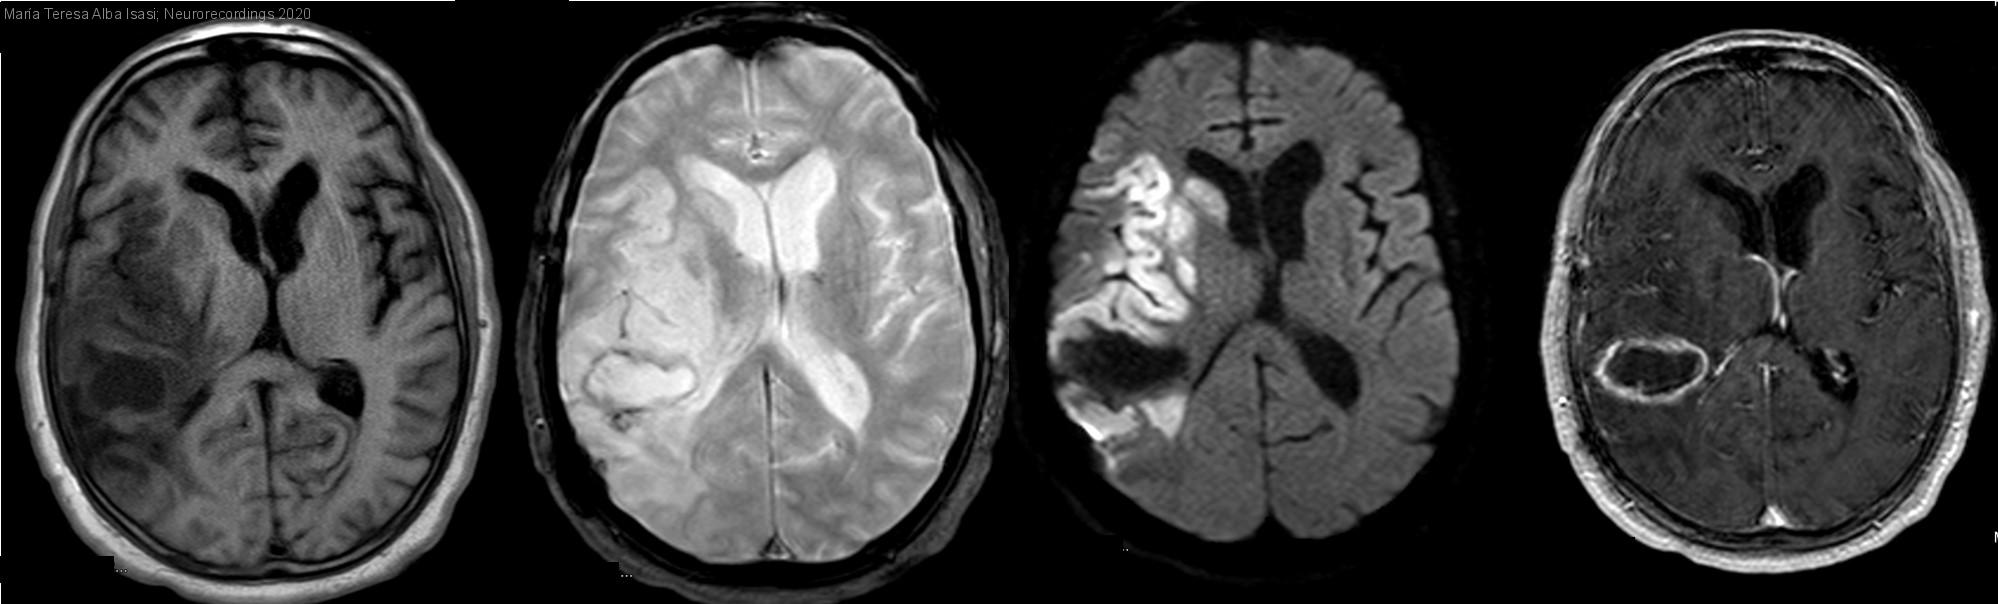

Déficit neurológico en paciente con antecedente de metástasis cerebral, ¿ictus o stroke mimic?

Déficit neurológico en paciente con antecedente de metástasis cerebral, ¿ictus o stroke mimic?

Diagnóstico final: Infarto fragmentado en territorio de ACM derecha y recidiva de metástasis cerebral

Neurología: Patología cerebrovascular | Neurooncología

Etiología: Ictus | Neoplasias

Varón de 52 años, exfumador y dislipémico, con antecedente de adenocarcinoma de pulmón estadio IV que precisó, el año pasado, resección del tumor primario y de metástasis cerebral única parietooccipital derecha, y tratamiento con radioterapia y quimioterapia. Es encontrado...